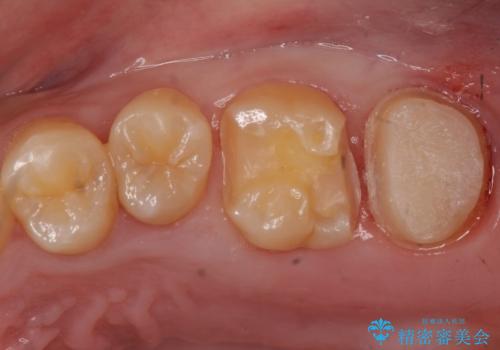

- 奥歯に穴が開いた気がするとのことで来院。

検査の結果、左上の奥歯に大きな虫歯があることが確認できました。

患者様のご希望もあり、今回はセラミックでの治療となりました。

- 左上6:セラミックインレー/77,000円 左上7:仮歯+ジルコニアクラウン/11,000+110,000円費用は治療当時の料金となります